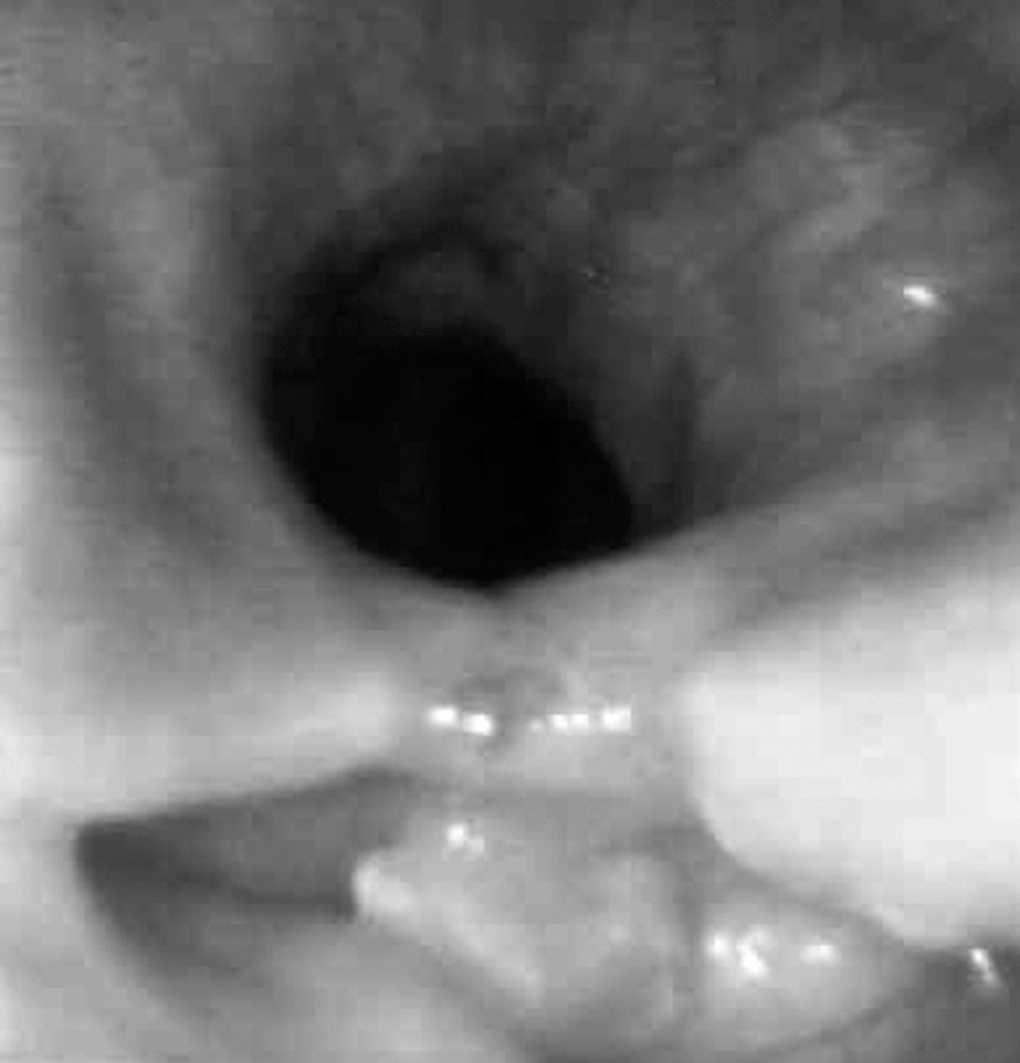

La cricofaringotomía se completó en una única sesión en los 3 casos. Ningún paciente sufrió incidencias ni complicaciones inmediatas o tardías y todos fueron dados de alta a las 48 h. La disfagia desapareció completamente en los 3 pacientes y el control endoscópico realizado a las 4 semanas del procedimiento mostró la cicatrización completa de la incisión y la patencia del paso a la luz esofágica a pesar de la persistencia del saco diverticular (fig. 4). Tras 12, 18 y 17 meses de seguimiento no ha reaparecido la disfagia ni otros síntomas atribuibles al divertículo de Zenker. La paciente 1 no precisó más intervenciones endoscópicas urgentes para colocar la sonda nasogástrica de aspiración como tratamiento de sus crisis suboclusivas de repetición a consecuencia del síndrome adherencial secundario a una resección intestinal por angiodisplasias y falleció a los 12 meses por causas cardíacas. El paciente 2 fue tratado con éxito del esófago de Barrett mediante una ablación endoscópica con plasma de argón.

Fig. 4. Paciente 2. Control a las 4 semanas. La incisión ha cicatrizado completamente. El paso a la luz esofágica (superior) es patente. El divertículo residual (inferior) contiene un pequeño resto alimentario.